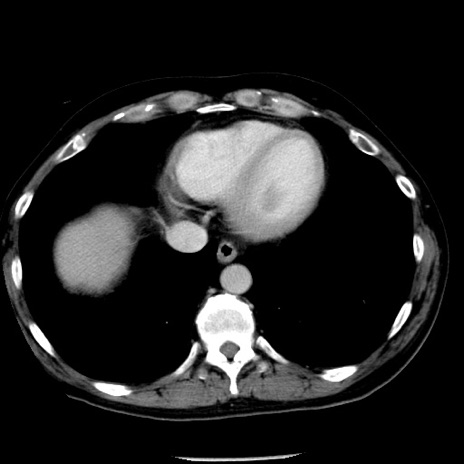

症例29(横断像)

【症例】40歳代男性

【現病歴】2日前から胃痛あり。徐々に周期的な激痛に変化した。本日になっても激痛があるため受診。

【身体所見】意識清明、BT 38-39℃台あり、腹部:膨満、やや硬、右下腹部に圧痛あり。

【データ】WBC 8500、CRP 23.26